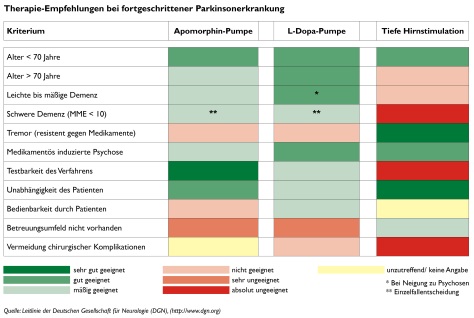

Für den fortgeschrittenen Morbus Parkinson stehen drei gute Behandlungsmethoden zur Verfügung, über die sich jeder Betroffene bereits frühzeitig informieren sollte. Sie haben das Ziel die Selbstständigkeit des Patienten zu erhalten und seine Lebensqualität zu steigern.

Kontinuierliche Apomorphin-Infusion

Kontinuierliche L-Dopa-Infusion

Tiefe Hirnstimulation